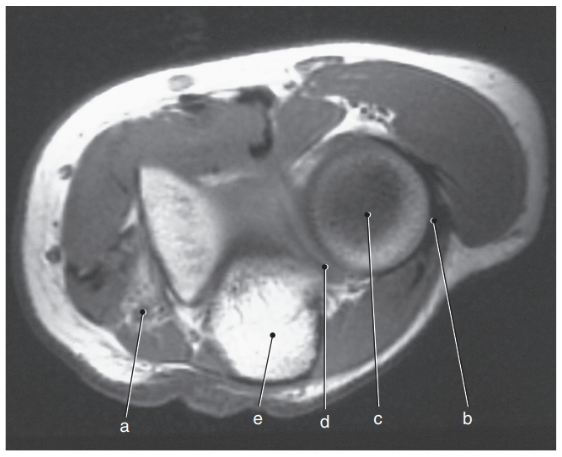

What is letter a?

Median nerve

What is letter e ?

Olecranon process

What is letter a ?

Lateral epicondyle

What is letter c ?

Coronoid process